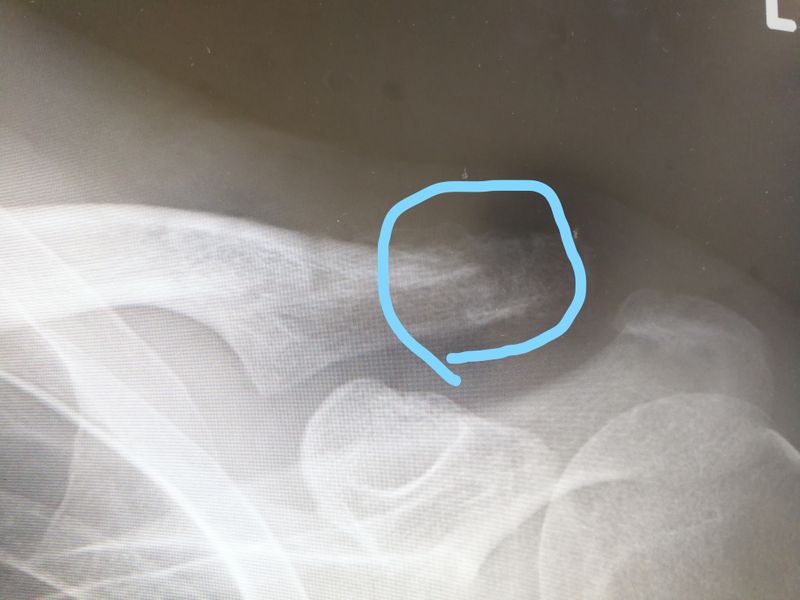

鎖骨プレートを外して2週間目の抜糸

今日は抜糸でした。

抜糸といっても、例によってテープを剥ぐだけの簡単なお仕事です。

いや、実際はレントゲン撮って経過観察もしてもらうので、誰でも出来る楽な仕事ではありませんが(笑)

もっとハッキリとした白になるまで、重い物は持てません。

とは言え、お蔭様でプレートが入っている時とは比較にならない程ラクです♪

フックプレートは痛いよ(;´Д`)